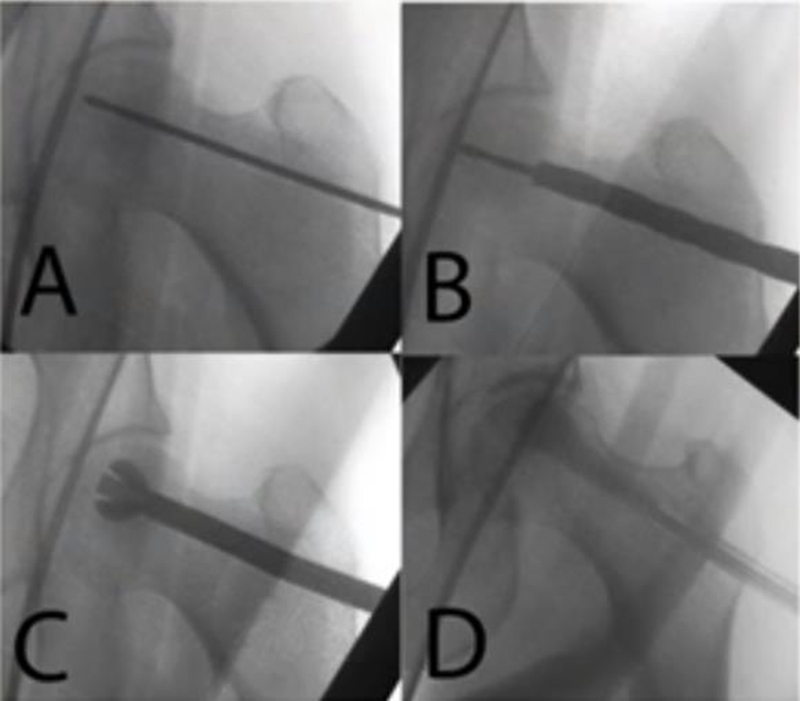

2、细孔径双通道钻孔髓芯减压术

1987年起,浙江省中医院团队设计粗隆下5mm孔径、双通道、股骨头倒V形钻孔加丹参灌注,治疗成人股骨头坏死54例,经过2~8.5年临床观察显示,该方法疗效明显,总优良率达81%,Ⅰ~Ⅱ期优良率达94%。

该疗法手术创伤小、难度小,对患者负影响较小,术后机能恢复快,易于接受。